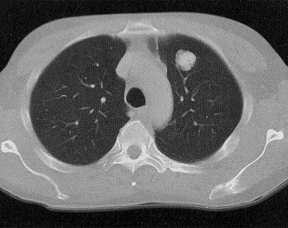

“Lung cancer is one of the most common types of cancer in the UK, but it’s hard to treat with a high relapse rate,” Charles Swanton, FRCP, BSc, PhD, medical oncologist at University College London Hospitals, deputy clinical director and head of the Cancer Evolution and Genome Instability Laboratory at the Crick, chair in personalized cancer medicine at the UCL Cancer Institute, chief investigator of the TRACERx study, and senior author of this study, stated in a press release.2 “It’s vital to understand who would benefit from more aggressive treatment, especially for patients with stage I disease who are often diagnosed during CT screening for those at a higher risk. Using sensitive ctDNA tests is one way to do this, which we hope will maximize clinical benefit and minimize unnecessary treatment for individual patients.”